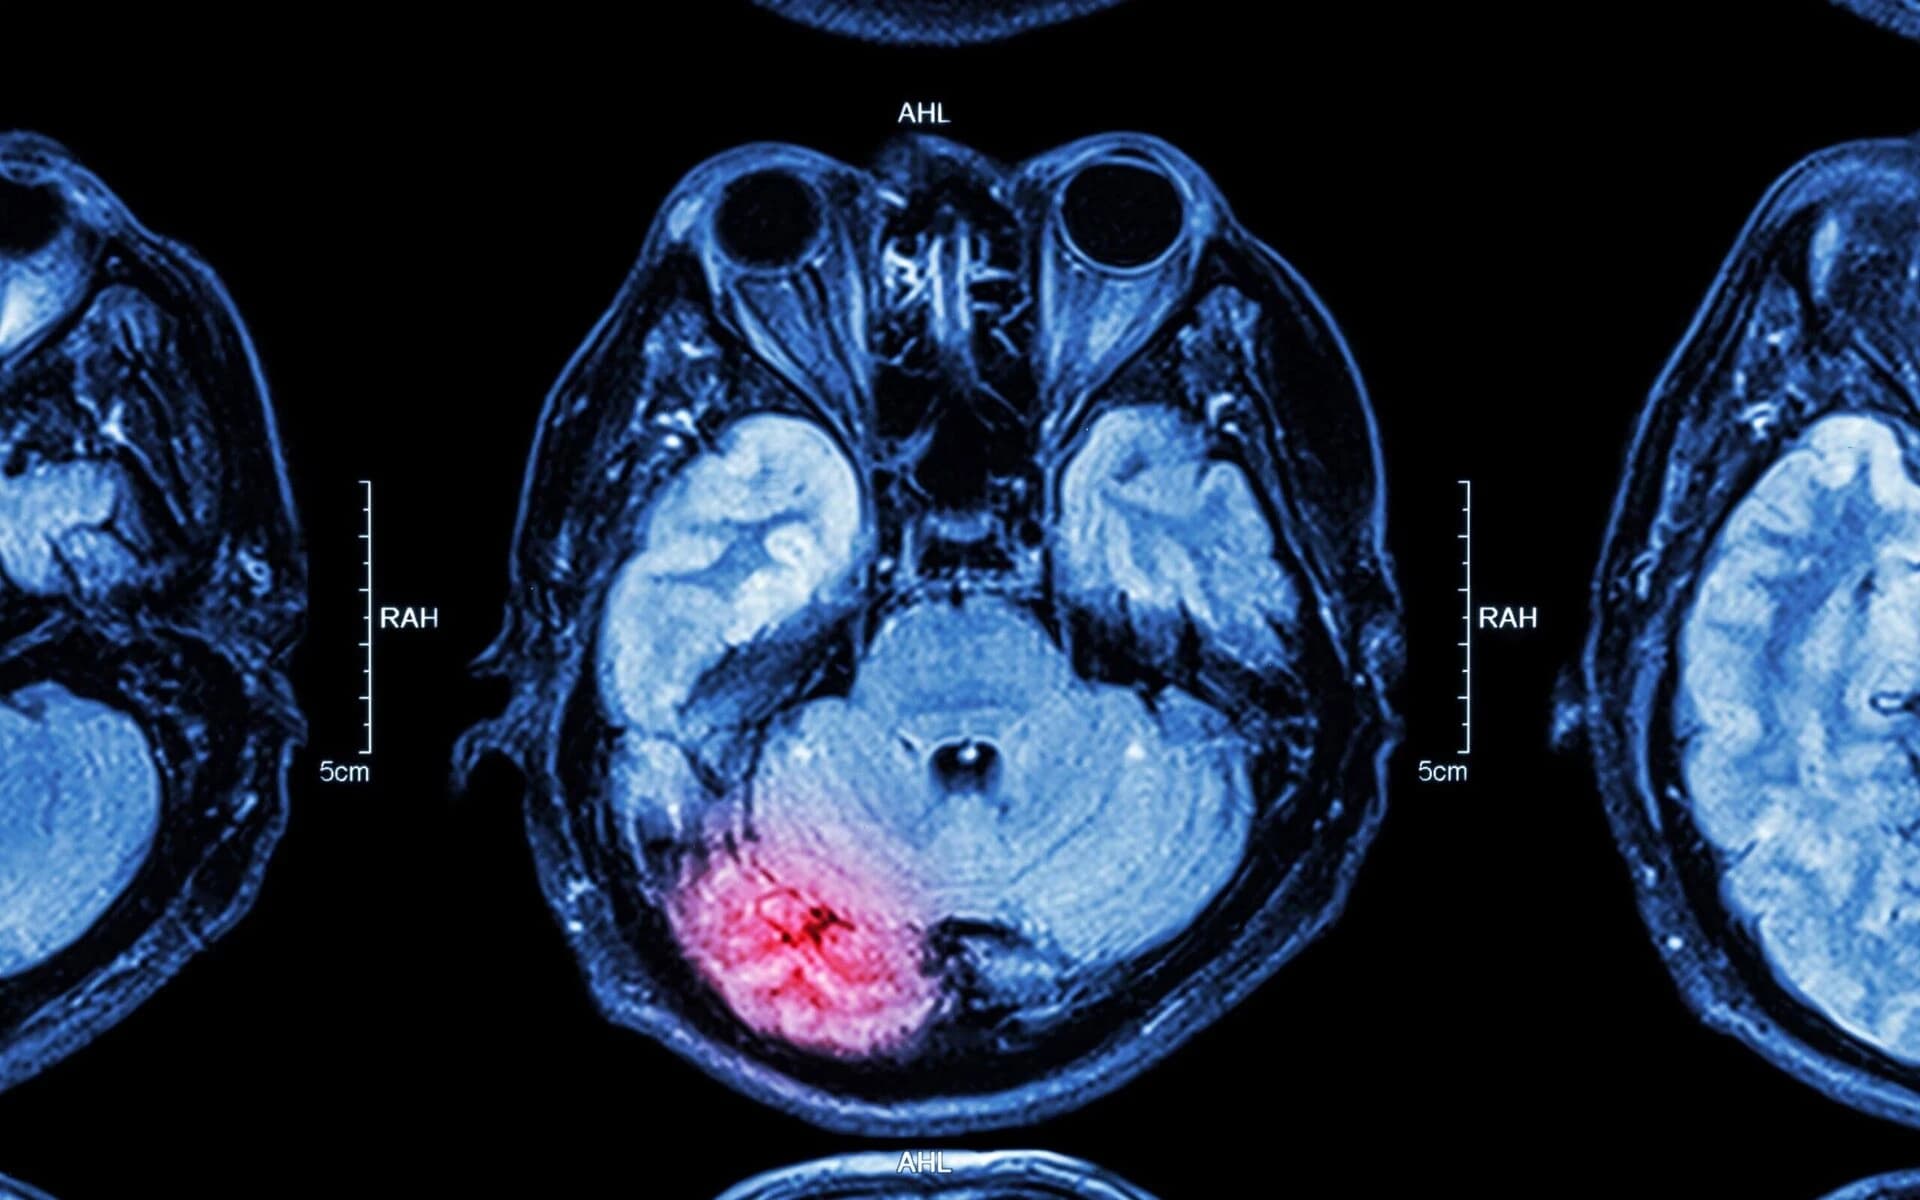

Brain Hemorrhage

Bleeding in or around the brain requiring emergency surgery and extensive rehabilitation.

Brain injuries are proven through medical documentation including CT scans, MRIs, neuropsychological testing, and expert testimony. We work with neurologists and brain injury specialists to build compelling evidence of your injury and its impact on your life.